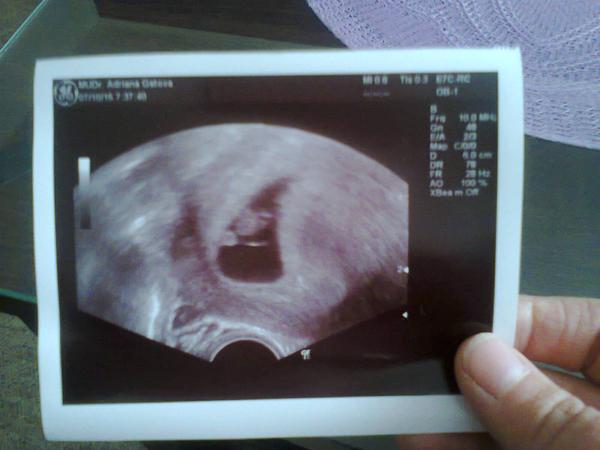

Ahojte dievcata, tak dnes som bola na potvrdenie tehu. Vseto vyzera byt v poriadku, mimi je v maternici,srdiecko vraj bilo,aj ked ja som ho tam ani za boha nevidela, mimco malo 0,58 cm co vraj zodpoveda 6+3tt a podla MS by som mala byt 6+5tt. Mam prist o tri tyzdne este na hedno potvrdenie akcie,ze sa vsetko dobr vyvyja a potom o dalsie tri tyzdne prva poradna. A o tyzdnem mam ist na odbery. Na jednej strae som strasnw stastna,ze je vsetko ok,no na druhej budem dalsie 3 tyzdne trpnut,aby bolo vsetko ok.